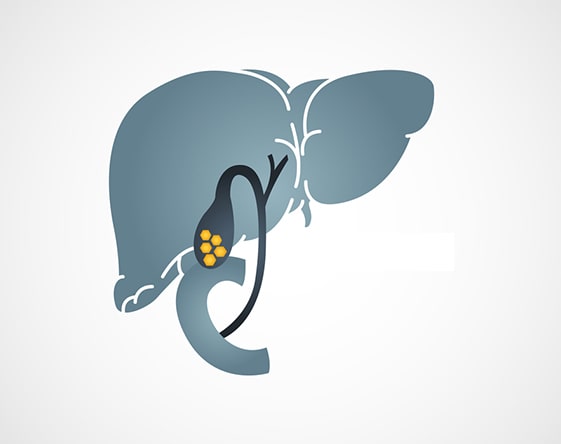

Cholangioscopy

Diagnostic and therapeutic intervention of the bile ducts. It is one of the noninvasive...

Laser Lithotripsy

Laser aided stone removal for complicated gallstone disease.When complicated, large...

Liver Elastography

Diagnosis & assessment of chronic liver disease. It is a non-invasive medical imaging...

I had stomach pain and yellow color in my eyes. I was diagnosed to have Jaundice and gallbladder stones. I had to undergo the ERCP procedure and I must say I was very anxious. I would like to thank all staff, doctors, and helping staff for their care and treatment. I was discharged yesterday after the successful removal of stones.

My father was suffering from jaundice and pain in the stomach. He was diagnosed with multiple stones in gallbladder and liver. He was advised to undergo surgery which was difficult because of his heart condition. I found the Laser Lithotripsy procedure at SR Kalla Hospital. Thanks to doctors for treating my father and making him well.

Jaundice is caused by a buildup of bilirubin, a waste material, in the blood. An inflamed liver or obstructed bile duct can lead to jaundice, as well as other underlying conditions. Symptoms include a yellow tinge to the skin and whites of the eyes, dark urine, and itchiness.

ERCP is a procedure that is adopted to diagnose the disease-related liver, gallbladder, pancreas, and biliary system. With a help of a special endoscope, the inside of the digestive system is examined. Laser Lithotripsy is an advanced procedure that uses a laser to break down the stones found in the ureter, kidney, and gallbladder.